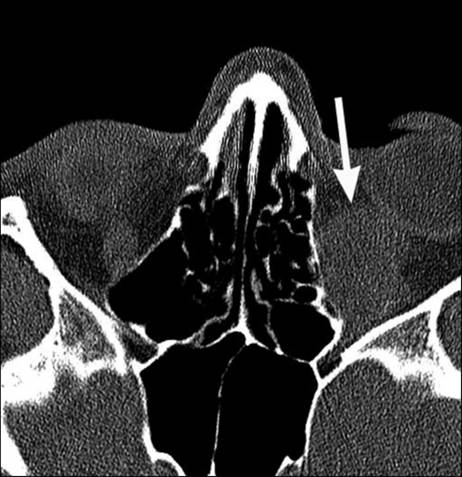

Рис. 6. Компьютерная томограмма. Ос-кольчатый

перелом нижней стенки глазницы (стрелка)

КТ: дефект костной стенки глазницы, смещение

костных отломков (симптом «ступени»). Косвенные признаки: кровь в околоносовых

пазухах, ретробульбарная гематома и воздух в ретробульбарной клетчатке (см.

рис. 6).